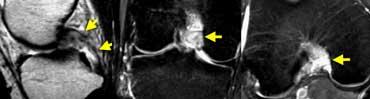

Lưu ý rằng trên ảnh mặt phẳng vành và mặt phẳng ngang, các bó sợi ACL nằm sát ngay bên cạnh xương của hõm liên lồi cầu (mũi tên).

Tuyệt đối không được có dịch giữa các bó sợi ACL và xương lồi cầu ngoài (gọi là ‘dấu hiệu hõm rỗng’).

TRÁI: Các bó sợi ACL có hướng bình thường nhưng không bám vào lồi cầu đùi. PHẢI: Dấu hiệu hõm rỗng: dịch áp sát mặt trong lồi cầu ngoài.

Đôi khi dễ đánh giá hơn liệu các bó sợi có còn bám vào xương hay không khi quan sát trên mặt phẳng vành.

Tuyệt đối không được có dịch áp sát mặt trong lồi cầu ngoài.

Nếu có dịch ở vị trí này, được gọi là ‘dấu hiệu hõm rỗng’, cho thấy ACL đã bị bong khỏi điểm bám trên lồi cầu đùi.

Trên mặt phẳng ngang có dấu hiệu hõm rỗng (mũi tên vàng) ở vị trí lẽ ra ACL phải bám vào lồi cầu. Ở mức thấp hơn (sang phải), ACL đứt đã dính sẹo vào PCL (mũi tên xanh lá).

Trên mặt phẳng ngang cũng phải thấy dây chằng nằm sát bên lồi cầu.

Ở mức thấp hơn, chúng ta thấy ACL đứt bám dính vào dây chằng chéo sau.

Chúng đã dính vào nhau thành sẹo.

Đây là hình ảnh rất thường gặp trong đứt ACL mạn tính.

Sự dính sẹo này tạo ra góc gấp cấp tính của dây chằng.

Mặc dù ACL đã dính vào PCL, nhưng vẫn không đủ vững và cần phải tái tạo.